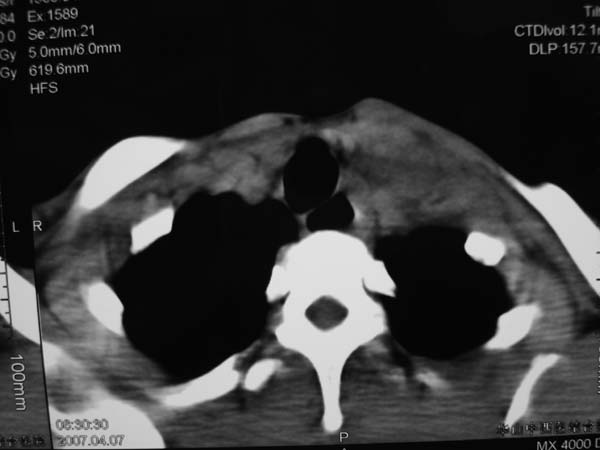

患者男性,37岁,农民,自觉左颈部肿大三天,无其它不适。

病灶边界较清,密度不均,其内可见坏死灶,左侧甲状腺受压,考虑神经源性肿瘤可能性大,建议穿刺活检。

支持左侧神经源性肿瘤。

病灶边界较清,密度不均,其内可见坏死灶,左侧甲状腺受压,考虑神经源性肿瘤可能性大。